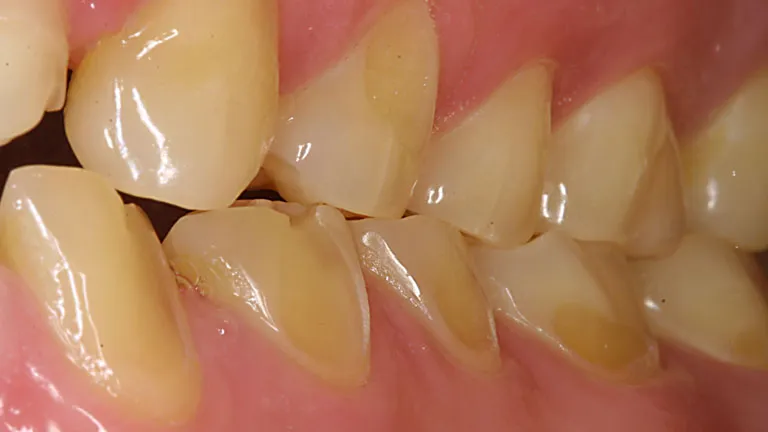

Regularne i zbyt intensywne szorowanie zębów sodą to prosta droga do nieodwracalnego starcia szkliwa. Szkliwo jest najtwardszą tkanką w ludzkim organizmie, ale raz uszkodzone, nie regeneruje się. Kiedy szkliwo jest ścierane, zęby stają się bardziej podatne na próchnicę, ponieważ bakterie mają łatwiejszy dostęp do zębiny. Co więcej, uszkodzone szkliwo odsłania zębinę, która jest znacznie bardziej wrażliwa. To właśnie ona zawiera kanaliki z zakończeniami nerwowymi. W efekcie pojawia się ból i nieprzyjemna nadwrażliwość na gorące, zimne, słodkie, a przede wszystkim kwaśne pokarmy i napoje. To dyskomfort, który może znacząco obniżyć jakość życia.

Problem, o którym się nie mówi: Podrażnione i krwawiące dziąsła

Nie tylko szkliwo jest narażone. Zasadowy charakter sody oczyszczonej, w połączeniu z jej ścieralnością, może być bardzo drażniący dla delikatnych tkanek dziąseł. Regularne stosowanie sody może prowadzić do ich podrażnienia, zaczerwienienia, a nawet krwawienia. W dłuższej perspektywie istnieje ryzyko recesji dziąseł, czyli ich cofania się, co odsłania szyjki zębowe i sprawia, że zęby wydają się dłuższe, a także stają się jeszcze bardziej wrażliwe. To poważny problem estetyczny i zdrowotny, który jest trudny do wyleczenia.